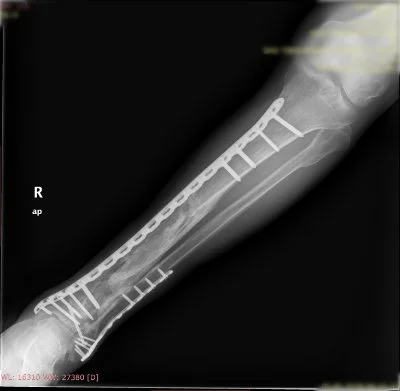

Görüntüleri büyütmek için resmin üstüne tıklayınız.